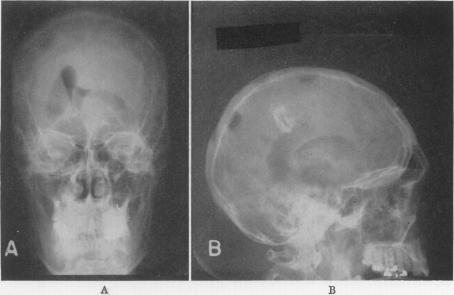

Brain abscess associated with pulmonary angiomatous malformation.

Ann Surg. 1953 Oct;138(4):521-31. doi: 10.1097/00000658-195310000-00005.